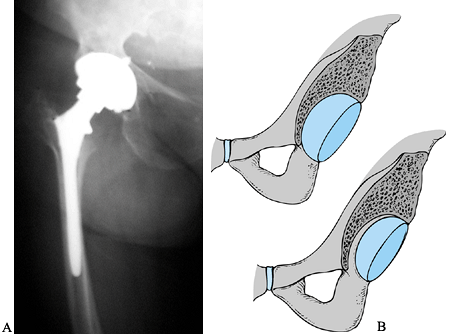

This approach provides excellent exposure because the trochanter is

detached from the femur and reflected superiorly with the gluteal

muscles attached (Fig. 106.25A). In revision

surgery the proximal femur is often damaged and the greater trochanter

is compromised by osteolysis. This factor has significant drawbacks in

the reattachment of the trochanter. Healing is usually fibrous, and

fixation of the small proximal segment is difficult, even with the use

of claws and grips.

Figure 106.25. A: Sagittal view of the trochanteric osteotomy. B: Sagittal view of the trochanteric slide.

|

trochanteric slide involves an osteotomy of the anterior trochanteric

bone, which is reflected anteriorly in continuity with the gluteus

medius and vastus lateralis. Make the osteotomy just lateral to the

gluteus minimus insertion, or alternatively, it can be made thicker to

include the gluteus minimus with the fragment. Reattach the slice of

trochanter with cerclage wire around the lesser trochanter and through

the bony fragment. Stability is usually excellent following

reattachment owing to the opposing pulls of the gluteus medius and

vastus lateralis (Fig. 106-25B). The trochanteric slide can improve visualization in the difficult primary arthroplasty as well as the revision. In addition,

the dissection can be extended proximally for exposure of the ilium

with less risk to superior gluteal neurovascular structures as can be

encountered with the modified Hardinge approach (39).

The mobility of the trochanteric fragment has the advantages of

re-establishing abductor tension and facilitating fixation to a

proximal femoral allograft.